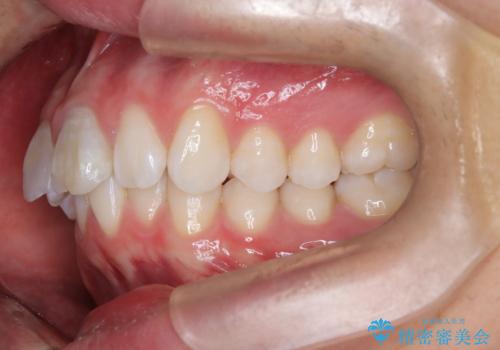

【ワイヤー矯正 11ヵ月で矯正終了!】歯のでこぼこを治したい!

- 「歯のでこぼこを治したい 1年くらいで矯正を終わらせたい」を主訴に来院された患者様です。

叢生量は多く無く歯の傾斜も標準傾斜だったので歯は抜かずにワイヤー矯正で治療を行いました。

左側は2級傾向が強く臼歯の遠心移動をご提案しましたが、1年以内に矯正を終わらせたいという患者様のご意向で希望されず叢生を改善する矯正となりました。